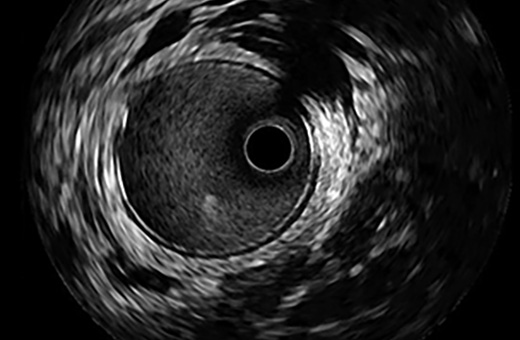

OPTICROSS Imaging Catheter 40 MHz

IVUS image of inside a coronary vessel using the 40MHz Opticross catheter

Axial resolution: 38 µm

High-Definition IVUS image quality helps physicians more accurately identify lesion length, assess plaque morphology, and determine the tools required for vessel prep. See how OPTICROSS HD’s 60 MHz images stack up against the competition.